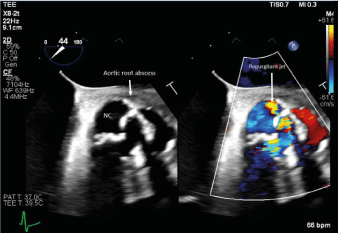

EKG demonstrated a new first-degree atrioventricular block.TEE revealed dilated ascending aorta at 4.3 cm (3.8 cm 1 month prior), aortic root abscess, prosthetic valve stenosis with a mean transvalvular gradient of 53 mmHg, leaflet thickening, and regurgitation through a perforated non-coronary cusp. (Figure 1) Blood cultures drawn 3 days before admission grew G. morbillorum.

Figure 1.TEE long axis demonstrating Trifecta 25 Bioprosthetic valve endocarditis (2D).Regurgitant jet through perforated non-coronary cusp (NC)